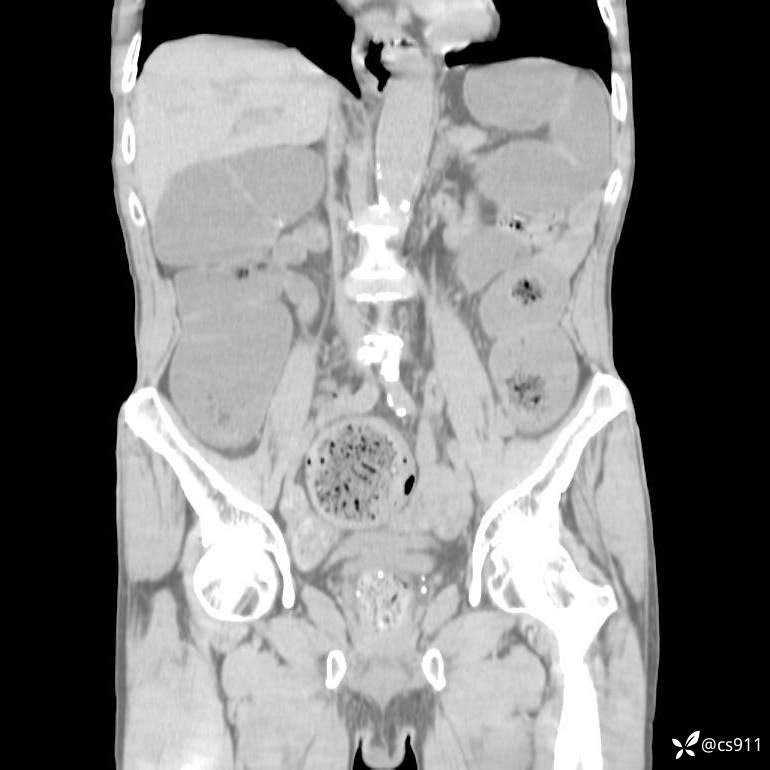

急腹症之急诊CT,原因?答案公布

男,77岁,腹痛、腹胀伴恶心呕吐1天。呕吐胃内容物,非喷射性呕吐,有咖啡色样胃内容物,诉有胃穿孔病史。查体:全腹平,下腹部压痛,全腹无反跳痛,叩诊呈浊音,移动性浊音阴性,肠鸣音减弱,1-2次/分。肛检:直肠未扪及明显肿物,可触及大量粪块。

T 36.6℃ P 80次/分 R 26次/分 BP 100/60mmHg

白细胞(WBC) H 14.55 10e9/L 4-10

中性粒细胞百分率(NEUT%) H 85.7 % 40-75

血淀粉酶(AMY) HH 1859 U/L 35-135

癌胚抗原(CEA) H 27.44 ng/ml 0-5

呕吐物 潜血试验 * 阳性 阴性

患者轮椅入室检查神志清楚, 能配合摆位和呼吸